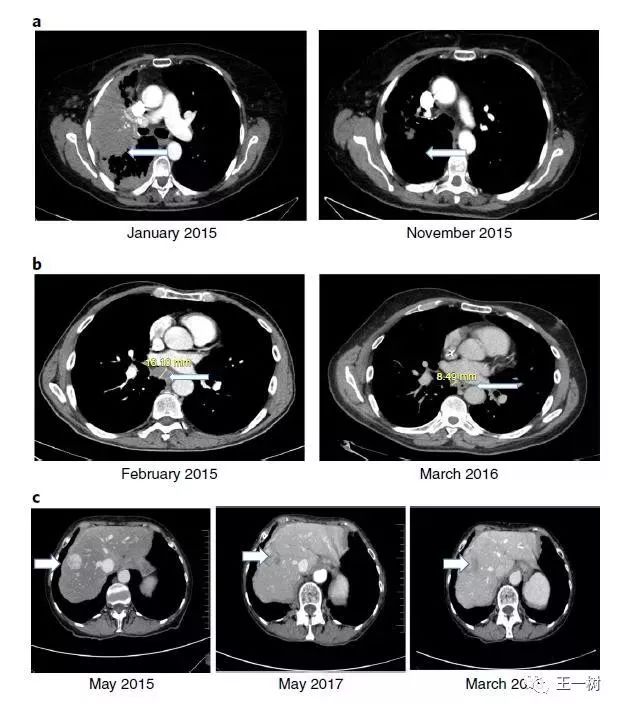

DNA及RNA变化指导治疗案例分享

图a)是一名72岁女性的NSCLC患者,在erlotinib联合pemetrexed治疗后进展,加入WINTHER研究,检测出EGFR T790M突变,接受了afatinib联合cetuximab的治疗(当时Osimertinib治疗T790M突变尚未获批),患者达到了CR (PFS 达13个月),治疗后的右图对比治疗前的左图可以看到明显的缩瘤。

图b)是一名68岁的的晚期肠癌男性患者,在Xelox方案和FOLFIRI方案后进展,加入WINTHER研究,经NGS检测出MSH6突变(一种错配基因导致MSI-H),接受了IO药物治疗,患者达到了PR(PFS>6个月)。同样可以在图中看到治疗后的明显缩瘤。

图c)是一名69岁的女性患者,分化良好的神经内分泌、小肠肿瘤和腹膜转移接受去瘤手术,并接受兰诺肽(长效生长抑素类似物)治疗残留疾病。之后接受过肠梗阻手术,并持续服用生长抑素,并加入其他临床试验进行过Axitinib10个月的治疗后进展。之后加入WINTHER研究,进行NGS检测未发现基因突变,但RNA检测发现AKT2和AKT3过表达,基于此给与了mTOR抑制剂Everolimus治疗,结果达到了疾病稳定,且PFS>34个月,同样可以在图中看到治疗后的明显缩瘤。